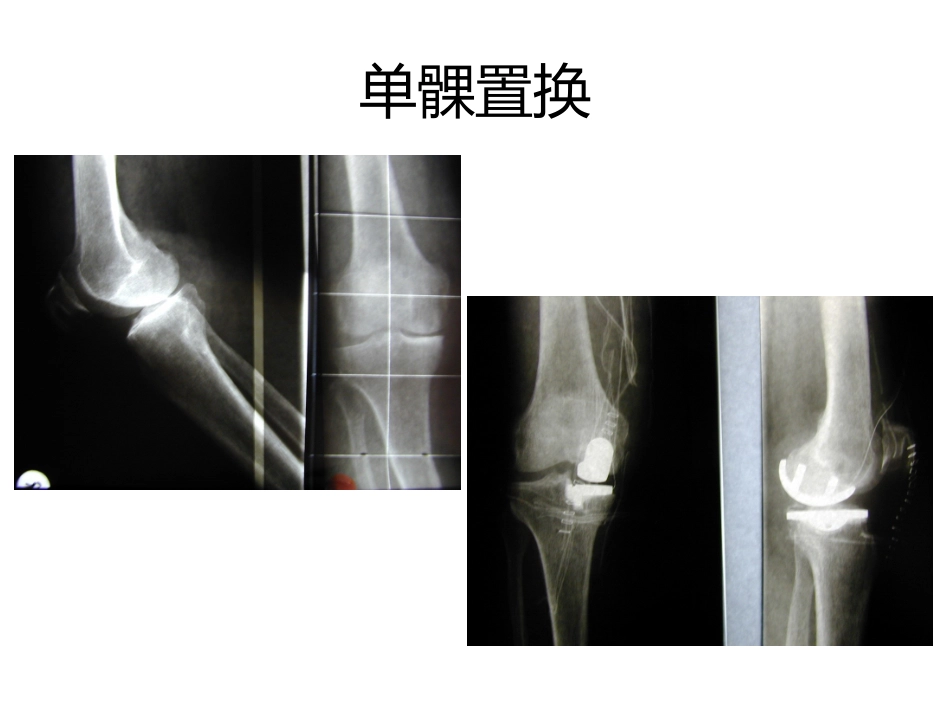

微创单髁置换MinimalInvasiveTechniqueofUnicondylarSled单髁置换•可用于内侧间室也可用于外侧间室单髁置换适应症•单间室病变,无其他间室软骨软化症•Rom>90度•被动纠正后膝内翻小于10度,外翻小于15度•关节韧带基本正常•非炎性关节炎,如OA,创伤性关节炎•体重小于90-95KG;BMI小于30禁忌症•炎性关节炎•多间室病变•韧带不稳,胫骨内外侧脱位大于3mm•ACL或PCL缺失微创——单髁置换髌旁<10cm切口无须将髌骨脱位截骨少软组织保护:大部分髌下脂肪垫,股内侧肌,髌上囊和股四头肌腱微创单髁置换——优点出血少,截骨少手术时间短术后疼痛少神经损伤少减少住院时间和费用康复快,患者更容易接受MITUS™单髁置换——缺点•适应症有限手术技•术较为困难需要一个较长的学习曲线•UKA的...